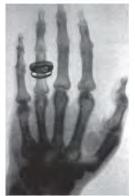

Зміни в будові внутрішніх

хірургічного втручання, застосувавши

випромінювання (іл. 8). Його використання є

(КТ), яка дозволяє отримувати тривимірні зображення органів. Ще більші можливості дає магнітно-резонансна томографія (МРТ). Низка методів скерована на вивчення функціонування внутрішніх органів: електрокардіографія реєструє електричну активність серця, електроенцефалографія головного мозку, спірометрія оцінює параметри дихання. Побачити внутрішні порожнини (шлунка, кишки) можна за допомогою тонких пристроїв з оптичними зондами ендоскопів.

Іл. 7. Гістологічне дослідження (вивчення будови тканини)

Іл. 8. Використання рентгенівського випромінювання в медицині